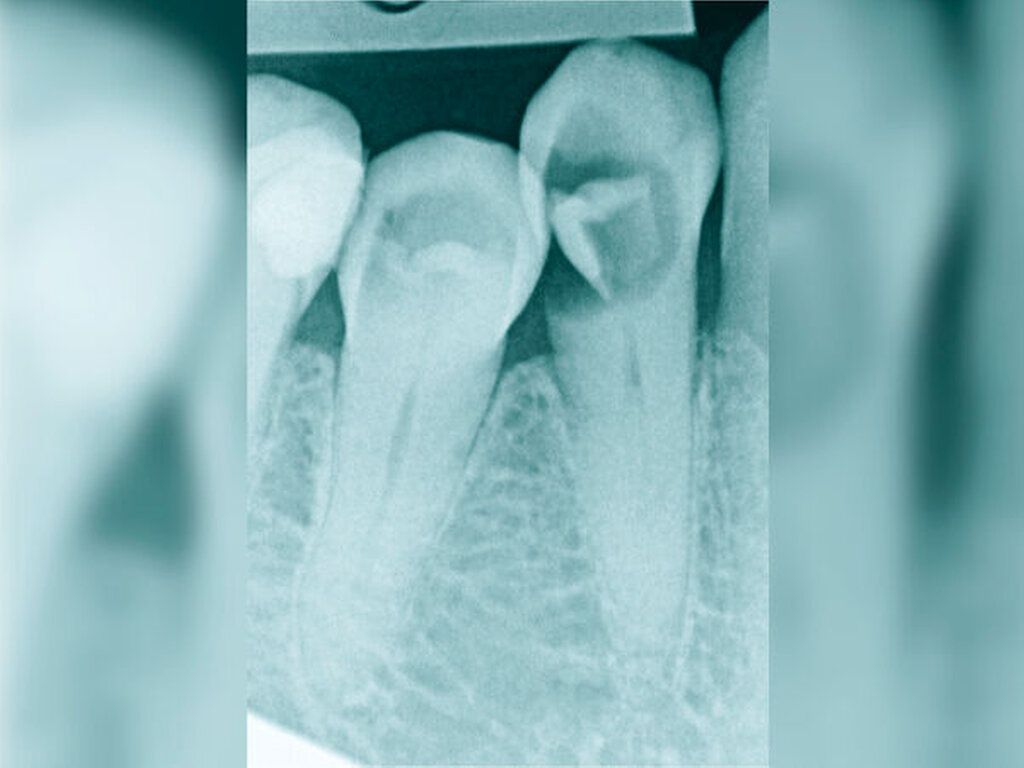

Die Schwierigkeit in der Therapie nimmt zu, wenn die Wurzelkanalkrümmung mehr als 30 Grad beträgt, der Krümmungsradius abnimmt (enge Krümmung) oder Mehrfachkrümmungen vorliegen [Duke et al., 2015; Pedulla et al., 2020]. Typisch für Mehrfachkrümmungen sind vor allem mesiale Wurzelkanäle unterer Molaren (Abbildung 4).

Sollte eine Konfluenz beider mesialer Wurzelkanäle am unteren Molaren vorliegen, kommt es zu einem abrupten Richtungswechsel und Instrumente können leichter frakturieren oder Stufen präparieren, so dass die Arbeitslänge nicht mehr erreicht werden kann.